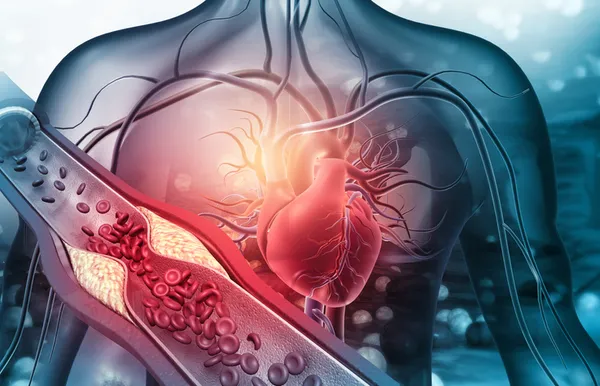

Ulusal Vasküler ve Endovasküler Cerrahi Derneği Başkanı Doç. Dr. Soner Yavaş ise kalp damar sisteminin hayat boyunca dinlenmeden çalışan sistem olduğunu vurguladı. "Kan basıncına karşı çalışıyor. Bunun için sürekli hastalıklara açık. Kalpten çıkan aort dediğimiz ana kanı taşıyan damar hayat boyunca yaklaşık 200 milyon litreye yakın kan geçiriyor içinden. Bütün organların ana dalları bu damardan çıkıyor. Bu damarda balonlaşma veya tıkayıcı hastalık görülebiliyor. En çok anevrizma görülüyor. En sık batın bölgesinde anevrizma gözükmekte. Yaş ile sıkıntı artmakta. Gençlerde de görülüyor. 65-74 yaş arasında 100 binde 55 görülme sıklığı var. Erkeklerde daha fazla tansiyon olması, tütün kullanımı, koah gibi hastalıklar da beyaz ırkta daha fazla görülmekte. Tanısı kolay aslında bu hastalıkların. Ne yazık ki toplumda bilinç oluşmamış durumda. Rutin kontrolde kolaylıkla saptanıyor. Tam bilinmediği için bazen çok gecikmiş hastalık olarak geliyor. En korktuğumuz damarın patlayarak gelmesi. Patlayarak gelen damarlarda ölüm oranı çok yüksek" diye konuştu.

Ulusal Vasküler ve Endovasküler Cerrahi Derneği Başkan Yardımcısı Prof. Dr. Nevzat Erdil, şah damarın beyni besleyen oksijen taşımasını sağlayan damar yapısı olduğunu hatırlattı. Bu damarda tıkanmaya bağlı insanlarda inme hastalığı olduğunu anlatan Prof. Dr. Erdil, ileri yaşa, sigara ve tansiyona bağlı bu hastalığın son dönemde gençlerde de rastlandığını söyledi.